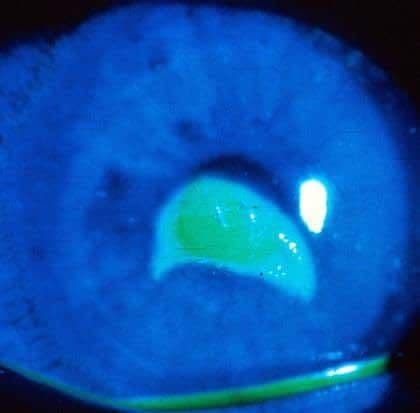

Зображення: абразія рогівки

Зобр. 19. Дефект епітелію БЕЗ інфільтрату.

Автор фотографії: CAPT (Ret) Joseph Pasternak, MD.

Зобр. 20. Дефект епітелію забарвлюється флуоресцеїном при підсвічуванні кобальтовим синім світлом.